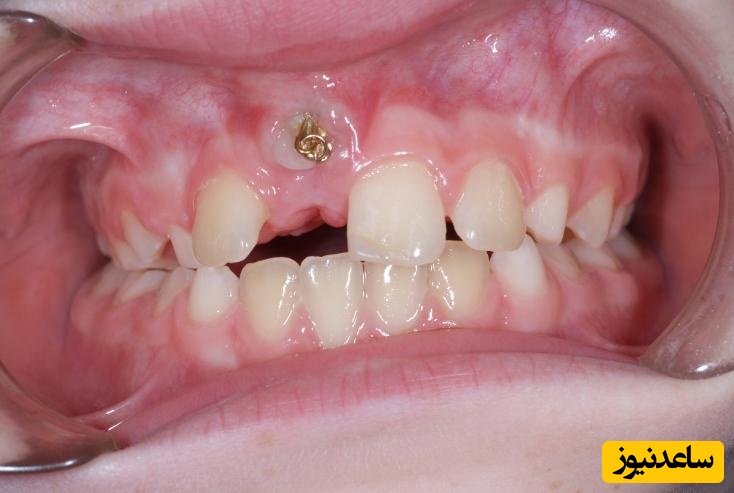

به گزارش سرویس سلامت ساعدنیوز، اگر در دهانتان دندانی دارید که بخشی از آن توسط لثه یا استخوان پوشانده شده است، به آن دندان غایب گفته می شود. حال سؤال اینجاست که چرا برخی از دندان ها غایب می شوند؟ در پاسخ به این سؤال باید گفت که علل مختلفی باعث بروز این مشکل می شود. از بین رفتن دندان های شیری در زمان نامناسب، دندان های متراکم و نبود فضای مناسب برای رشد دندان های جدید و قرار گرفتن جوانه دندان در شرایطی نامطلوب از جمله مهم ترین علل شکل گیری دندان های غایب به شمار می روند.

تحت تأثیر قرار دادن چهره و از دست رفتن زیبایی لبخند از دیگر مضرات دندان های غایب به شمار می رود. افراد بیمار مجبور هستند تا فضای خالی نامطلوبی را مابین دندان های خود تحمل کنند. بر طبق آمار دومین دندان فک فوقانی و دندان آسیای کوچک دوم در فک تحتانی از اصلی ترین دندان های غایب در میان بیماران شناخته شده اند. لذا همان طور که مشهود است، غیبت دندان دوم فک فوقانی می تواند تأثیر بسیار زیادی بر طرح لبخند بیماران داشته باشد.

بسته به نوع ناهنجاری و تعداد دندان های غایب متخصص ارتودنسی تصمیم می گیرد که کدام یک از روش های درمان دندان غایب را به کار گیرد. توصیه اولیه بر این است که فاصله بین دندان ها با ارتودنسی بسته شود. زیرا داشتن دندان های طبیعی مزایای مربوط به خود را دارد و با نگهداری صحیح از دندان های طبیعی می توان مادام العمر از وجود دندان های سالم بهره برد.در برخی موارد که سایز دندان ها کوچک است و یا تعداد دندان های غایب زیاد است متخصص ارتودنسی فاصله بین دندان ها را با دستگاه ارتودنسی مناسب تنظیم می کند و سپس اقدام به کاشت دندان یا ایمپلنت در بین فواصل دندانی می نماید.